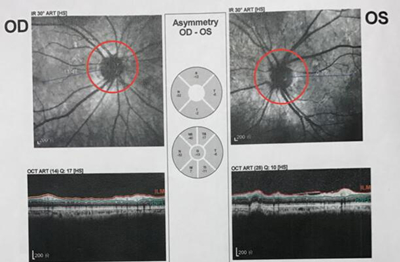

检查结果显示双眼视神经萎缩及视野缺损

于是邢主任给她做了进一步检查,通过OCT与视野计检查结果,邢宝刚主任判断张奶奶视野缺损的情况应该不是单纯的眼睛问题,极有可能是脑内肿瘤引起的。于是邢宝刚主任建议张奶奶去做脑部CT扫描检查。